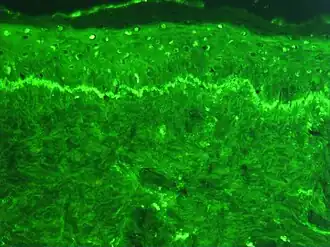

The histological hallmark of SLE is membranous glomerulonephritis with "wire loop" abnormalities.[38] This finding is due to immune complex deposition along the glomerular basement membrane, leading to a typical granular appearance in immunofluorescence testing.

Several techniques are used to detect ANAs. The most widely used is indirect immunofluorescence (IF). The pattern of fluorescence suggests the type of antibody present in the people's serum. Direct immunofluorescence can detect deposits of immunoglobulins and complement proteins in people's skin. When skin not exposed to the sun is tested, a positive direct IF (the so-called lupus band test) is evidence of systemic lupus erythematosus.[101]